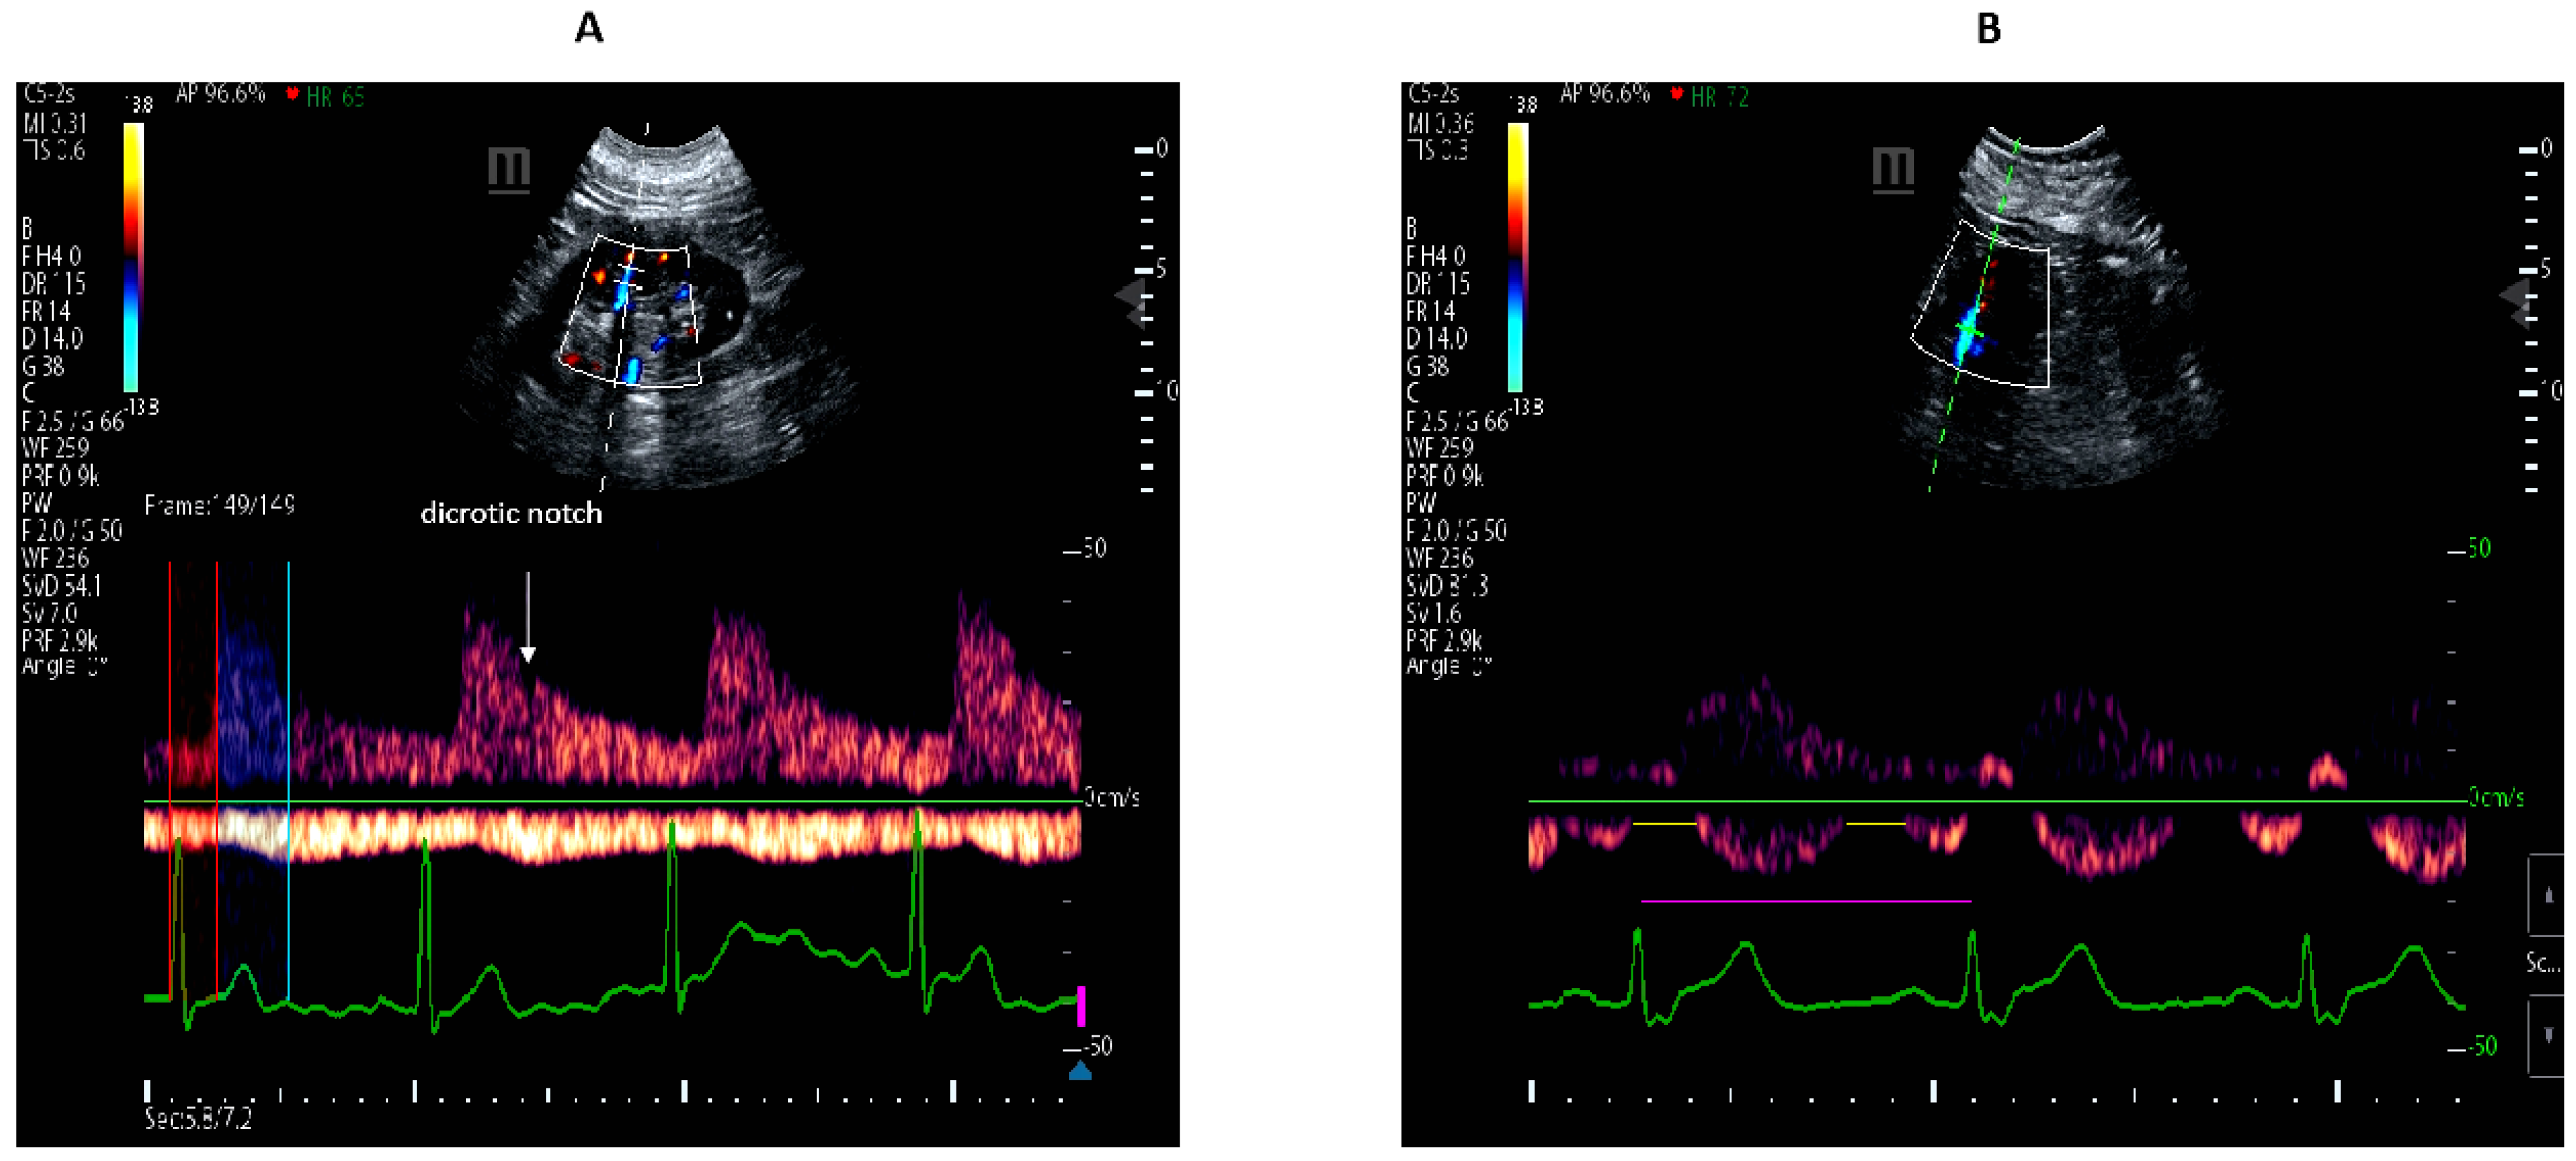

2.2. Color Doppler Ultrasonography